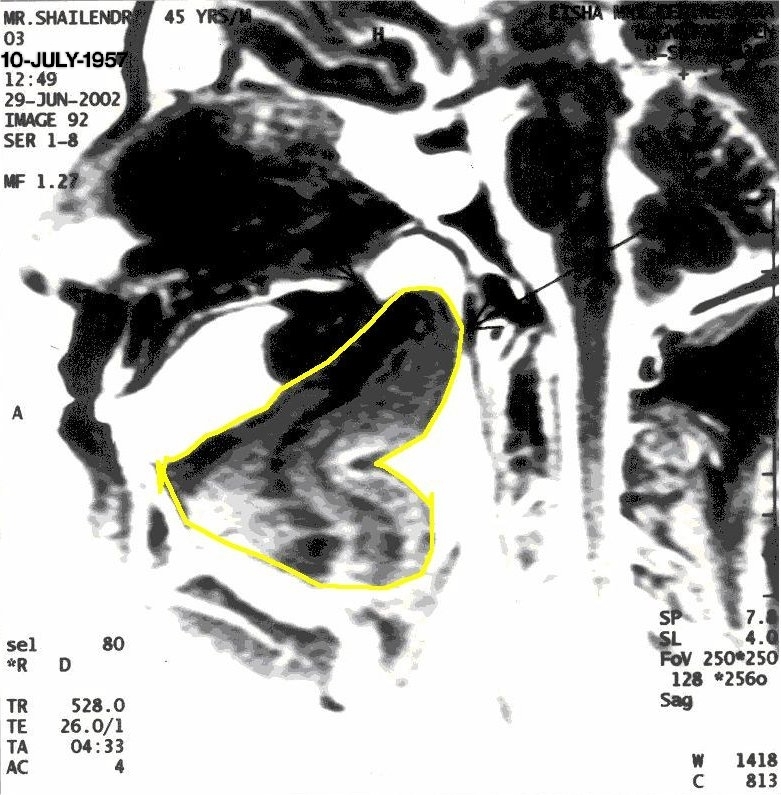

With Khechari Mudra

The position of tongue is outlined in yellow